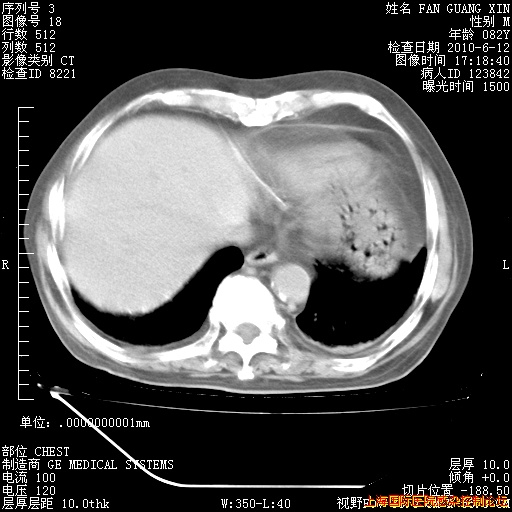

6月12日纵膈窗

回复

整整相隔30天的肺部CT好像有所好转啊。甲强龙减量第3天,需要观察体温。

海管,自昨日你和我通完话后,不知您岳父消化道症状有无缓解?体温怎样?阅读7.12日胸部ct,个人认为目前激素治疗是有效的,甲强龙减量是适宜的。因在抗痨治疗,需密切观察肝功、肾功能和血常规。不过,老年、长期住院和大量使用激素,很担心菌群失调发生